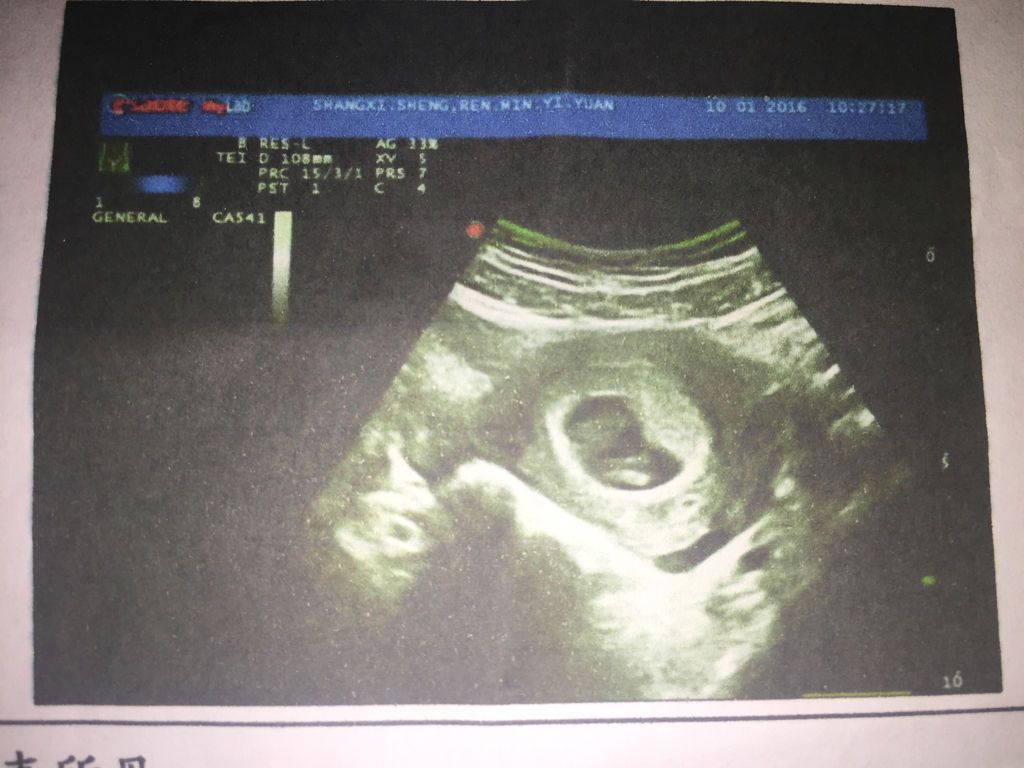

谁是妇产科大夫,帮我看看b超单这是同卵还是异卵?末次月经11.16日,怀孕53天测的,hcg正常吗

谁是妇产科大夫,帮我看看b超单这是同卵还是异卵?末次月经11.16日,怀孕53天测的,hcg正常吗?这个数值好吗?说明什么呢?

您好丰卫蒸,你现在怀孕7周半,hcg数值稍高,和怀双胞胎有截蛋关系,但是问题不大,佳裁建议继续观察! 希望我的回答能够对您有所帮助!望采纳!

你好,根据彩超结果看是同卵双胎,HCG数值是正常的。

这个hcg不算高了,相当于7周左右的水平。 正常。